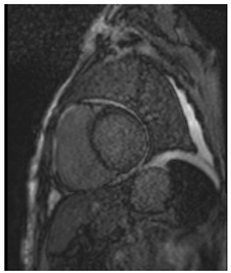

CMR can help differentiate amyloid CM from other infiltrative or hypertrophic cardiomyopathies. It is a complementary diagnostic tool to serological workup, bone scintigraphy, and endomyocardial biopsy. CMR can also offer prognostic and disease-monitoring ability. Cine steady-state free precession (SSFP) sequences examine the morphology and function of the four cardiac chambers. Like echocardiography, SSFP in amyloid CM shows increased LV wall thickness, atrial septal thickness, and valvular thickness with normal or reduced biventricular function. LV septal hypertrophy is mostly asymmetric in ATTR-CM and concentric in the majority of AL-CM [].

Amyloid deposition affects myocardial tissue architecture, which results in elevated intrinsic, non-contrasted myocardial T1 signal (native T1 mapping) []. The progression of amyloid CM can be quantitively monitored with native T1 elevation, which correlates with the degree of amyloid infiltration []. Amyloid fibril deposition can also cause myocardial edema. The increased water content in tissue prolongs T2 time, which is the relaxation time of protons in the transverse plane. However, T2 time in amyloid CM is usually shorter than that reported in myocarditis or myocardial infarction [].

Post-contrast CMR imaging provides information about the extracellular space, which in amyloid CM is distorted by amyloid deposition. In amyloid CM, TI-scout images for gadolinium kinetics show a simultaneous nulling of the blood pool and myocardium or a reverse null pattern where the myocardium nulls prior to the blood pool []. LGE patterns in amyloid CM range from absence to subendocardial or transmural, correlating with the severity of infiltration. LGE often involves all cardiac chambers. Contrast-enhanced T1-weighted imaging can be used to estimate extracellular volume (ECV), which is often markedly increased in amyloid CM (>40%) due to extracellular amyloid deposition []. Elevated ECV was shown to precede LGE in certain cases with a high probability of amyloid CM, likely signaling early disease []. However, the use of Gd to evaluate LGE and ECV may be precluded in patients with advanced kidney disease. Other contrast-free analyses of CMR that can help distinguish amyloid CM include longitudinal strain analysis. Similar to echocardiography, CMR shows globally reduced longitudinal strain in amyloid CM with relative apical sparing with specificity to distinguish CA of 82% but sensitivity of only 43% []. If Gd can be administered, the LGE ratio between base and apex, in addition to the relative strain ratio, was shown to have a higher discriminatory ability to distinguish amyloid CM from other causes of LVH []. Key CMR findings in amyloid CM are summarized in Table 1.